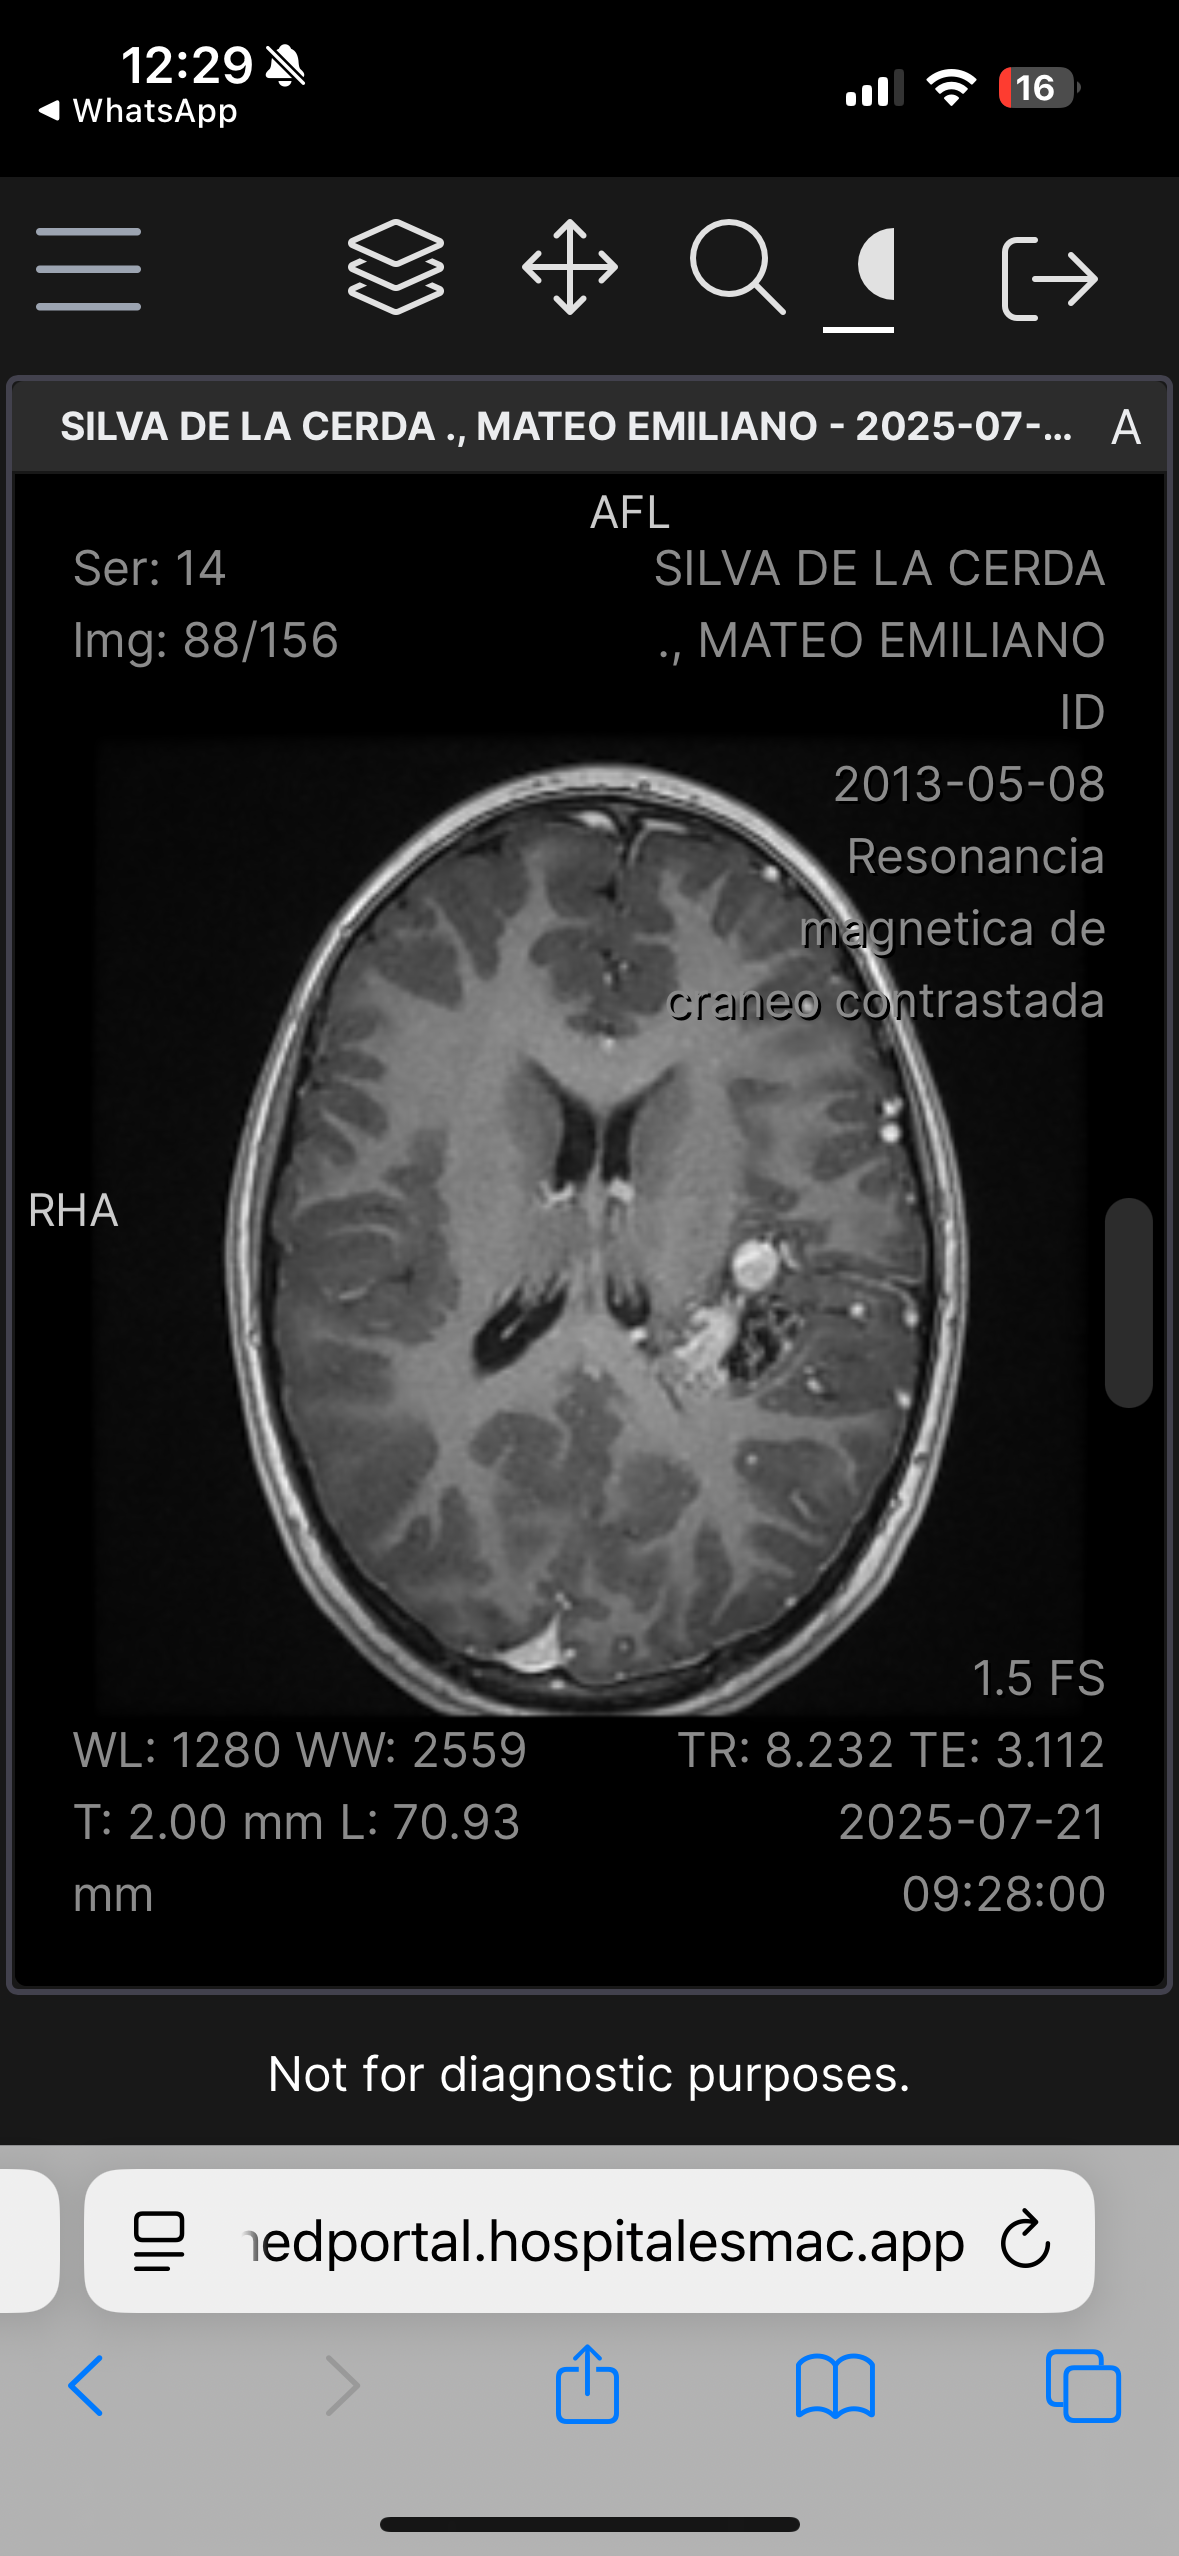

Hola, me llamo Mateo Silva De La Cerda, tengo 12 años, recientemente tuve un diagnóstico que cambió mi vida y la de mis papás, padezco una Malformación Arteriovenosa grado IV en la parte izquierda de mi cerebro, la cual hace un Nidus vascular. La complejidad de la malformación es por el aumento en la irrigación sanguínea los cual crea un tipo de “ nido” de venas y arterias, así como la profundidad en la cual se encuentra situada la malformación arteriovenosa en mi cerebro. Requiero una cirugía muy compleja, y la probabilidad de ocupar terapia intensiva posterior es muy alta.